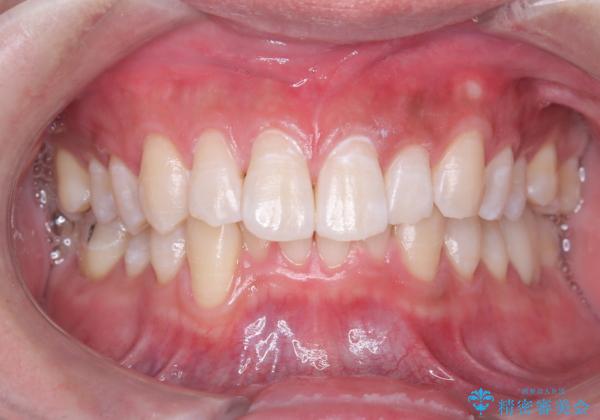

白い歯で清潔感get!初ホワイトニング

- 初めてのオフィスホワイトニングということで痛みなどの不安があったようですが、痛み等なくトーンアップし白くなりました。

- 29,700円費用は治療当時の料金となります

ホワイトニングは色味が段々と後戻りしてきてしまうため、定期的に受けていただいたりホームホワイトニングと併用していただくと白さを保つことができます。